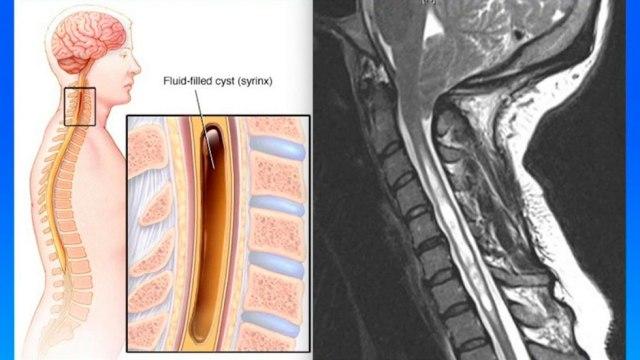

causas-y-tratamientos-de-quistes-en-la-columna-180321